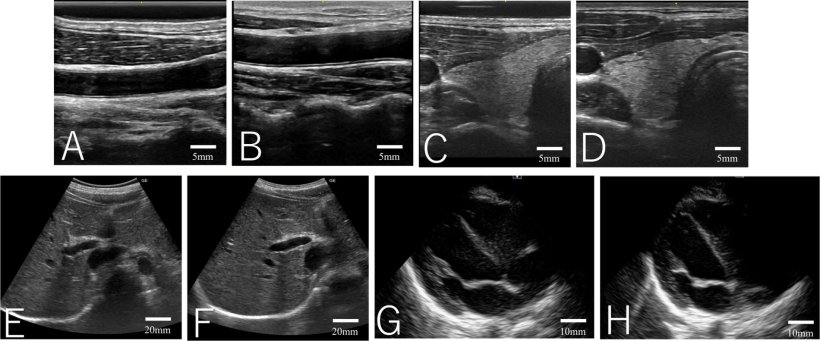

When compared directly with conventional liquid gel, the solid gel pad produced images of comparable quality across all examined sites. However, volunteer satisfaction was significantly higher when the solid gel was used. A major reason of patient discomfort is associated with the adherence of conventional liquid gel to chest hair and the difficulty of removal. The solid gel did not adhere to body hair and could be removed easily, resulting in reduced patient discomfort.